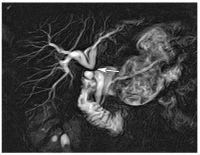

Choledocholithiasis

Abbildung 3: Choledocholithiasis. Die MRCP zeigt ein distales Choledochuskonkrement mit extra- und intrahepatischer Cholangiektasie.